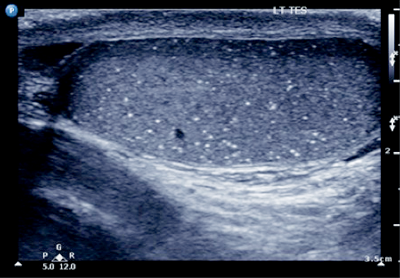

Right-sided testicular mass with associated microlithiasis.

Microlithiasis.

Five or more echogenic foci per high powered view, in either or both testes.